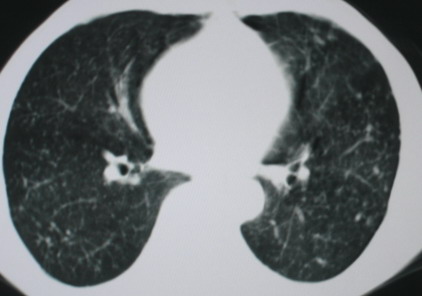

以下是引用医影拾贝在2008-6-3 18:48:00的发言:[br]双上肺弥漫性小结节影,纵隔窗内钙化淋巴结影,考虑血播性tb可能性较大,不除外肺ca可能

以下是引用卜一在2008-6-3 19:33:00的发言:[br]双肺结节,以双上肺分布为多,期间搀杂片状致密影及索条致密影。考虑:继发性肺结核伴血型播散可能性大。不除外肺泡ca的可能!另:椎体退变!

以下是引用panyishengct在2008-6-3 21:09:00的发言:[br]双上肺弥漫性小结节影,纵隔窗内钙化淋巴结影,考虑矽肺或/和tb可能性较大,不除外肺ca可能。腰椎考虑退变。 [br][br]